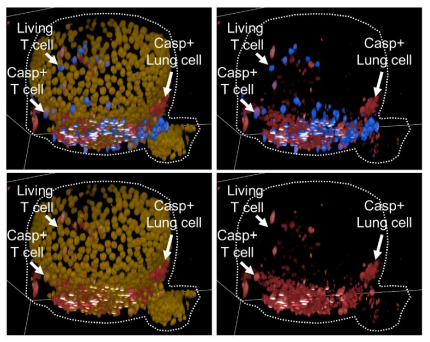

📢Postdoc alert! We are looking for a #postdoc with a strong interest in #leukemia and #proteomics to join our team Lund Stem Cell Center. ⬇️ Please RT - thanks!

It was an amazing experience to participate in the Molecular Hematopoiesis Workshop at #EHA2023 and present how we at @Hanssonlab are applying mass spectrometry-based proteomics to study fetal and adult hematopoiesis. Thanks again Britta Will, Mick Milsom and the organizers.